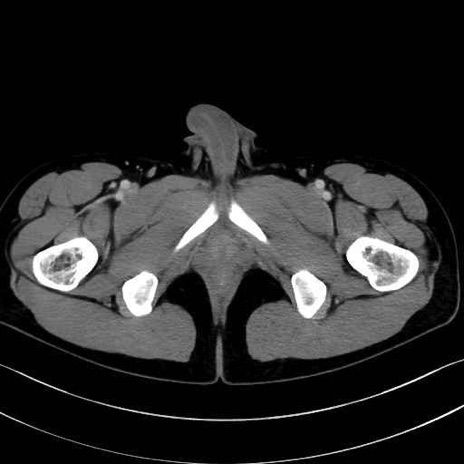

小殿筋 (Gluteus minimus)